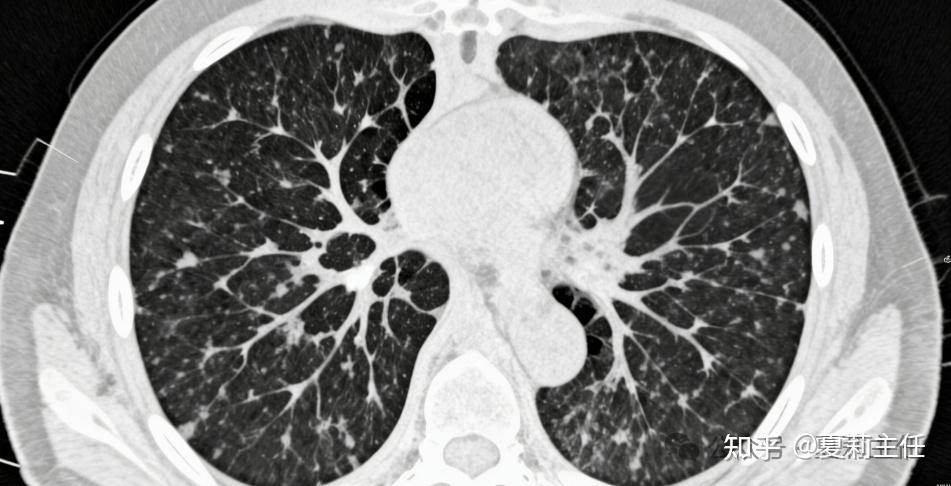

在肿瘤科诊室里,我见过太多患者听到 “浸润性肺癌” 这几个字时,眼神瞬间黯淡下来。大家都清楚,原位癌、微浸润癌相对安全,手术切除后基本能治愈;可一听到 “浸润性”,就难免直接和 “恶性程度高、预后不好” 挂钩,甚至一下子陷入绝望。

作为肿瘤科医生,我完全理解这份焦虑,但浸润性肺癌并非都是坏消息 —— 只要满足两个关键特征,5年生存率可接近100%,希望这份科普,能给迷茫中的你带去安心与力量。

这两个能带来 “好预后” 的特征其实并不复杂,我用大白话给大家讲明白:第一个是肿瘤以 “贴壁为主” 生长;第二个是 “高浸润成分占比不足20%”。

这两个特征结合在一起,本质上就是医学上的 “高分化浸润性肺癌”。我常跟患者打比方:高分化肿瘤就像肿瘤里的 “温和派”—— 它的细胞形态和正常肺细胞长得很像,没那么 “怪异”,也就意味着侵袭性、转移性都很弱,生长速度也相对缓慢。反观低分化肿瘤,细胞形态怪异,极具 “攻击性”,预后自然差一些。

大家担心浸润性肺癌,主要是怕它转移、难控制。但这类高分化的浸润性肺癌,因为恶性程度低,手术切除的效果非常好。而中分化、低分化的患者,有可能合并淋巴结转移,所以5年生存率数据没那么稳定,会有一定波动。

结合夏主任多年的诊疗经验:只要符合 “贴壁为主” 和 “高浸润成分不足20%” 这两个条件,通过规范的手术治疗,很多患者都能顺利回归正常生活,5年生存率更是接近100%,几乎和治愈没区别。